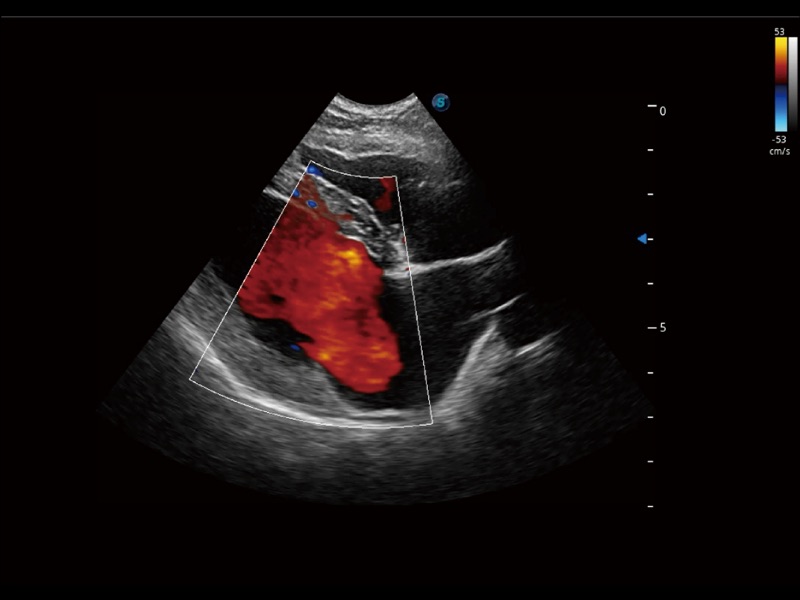

能够基于左心室壁追踪和辛普森法,自动计算射血分数,支持多个可移动点描迹,与手动测量相比,极大节省了动物医生的时间和精力。